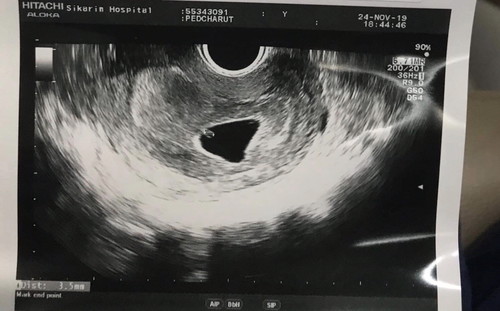

วันนี่มีเลือดออก เลยไปหาหมอ แต่ผลออกมาตกใจมากค่ะ หมอบอกว่าไม่พบตัวน้องในถุงตั้งครรภ์ มีแค่ถุงอาหารของตัวอ่อนเท่านั้นค่ะ หรืออาจจะท้องลม แต่หมอยังไม่ฟันธงว่ายังไง หมอบอกรอดูอีก 1-2 สัปดาห์ ถ้าไปซาวแล้วไม่เจอตัวคงต้องยุติการตั้งครรภ์ แม่ๆบ้านอื่นท่านไหนเคยมีประสบการณ์แบบนี้บ้างค่ะ (หรือมีใครแนะนำให้ไปซาวที่อื่นดูบ้างค่ะ)